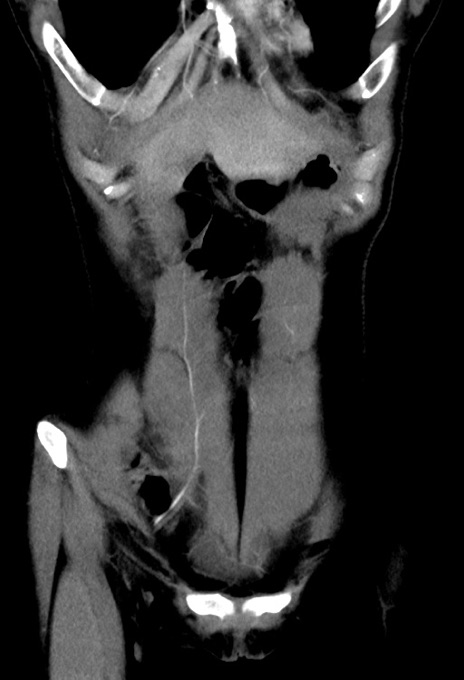

症例17(冠状断像)

【症例】20歳代女性

【主訴】嘔吐、下腹部痛

【現病歴】昨日夕食後に嘔吐し下腹部痛が出現。本日になっても嘔吐持続し改善しないため来院。

【身体所見】意識清明、BT 37.2℃、BP 108/67mmHg、腹部:平坦、やや硬、下腹部正中から右にかけて圧痛あり、反跳痛軽度あり、tapping pain(+)。

【データ】WBC 13600、CRP 14.94